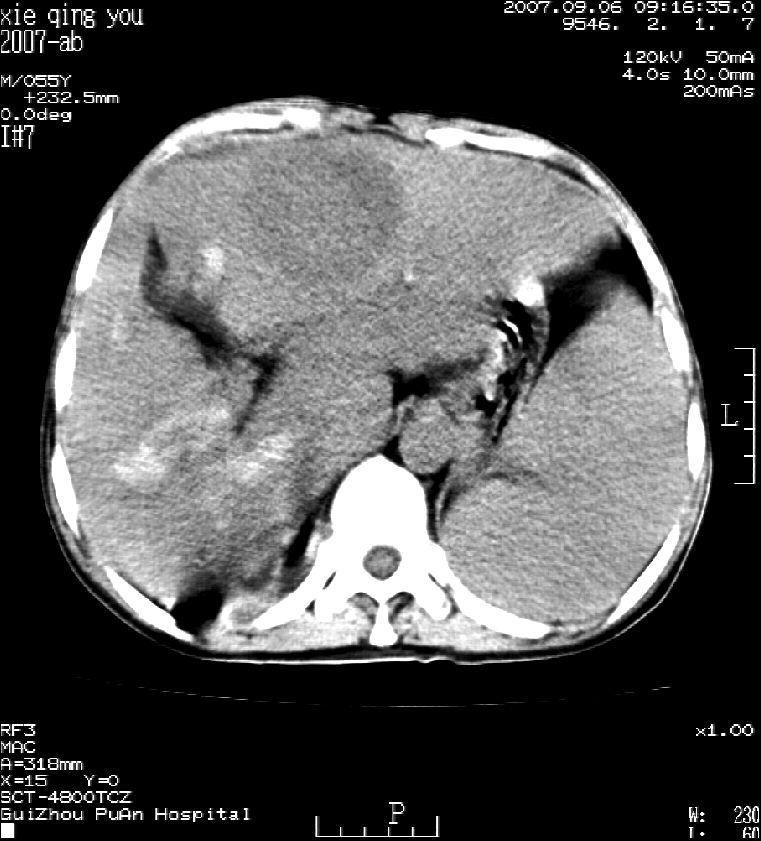

2007年8月片

2007年9月片

这个病灶很有意思,怎么可能没有了呢?我考虑当时很可能是肝脏脓肿(b超示囊肿是有可能误诊的,因为影像表现都是低回声吗?),现在脓肿吸收了,肝脏萎缩,肝裂增宽了.别的肝叶代偿增大,不过现在左内叶的确有个占位,肝内多发结石,脾脏比以前大,不排除有肝硬化可能.建议增强扫描给于定性!!!!

肝硬化\\脾大,肝左叶肝癌可能性大,建议增强扫描.肝内胆管多发性结石.

1, 肝硬化,脾大;2,肝左叶肝癌可能性大,建议增强扫描.3,肝内胆管多发性结石.

肝硬化、脾大、肝内胆管多发结石。肝左叶低密度占位。建议增强扫描.排除肝癌

肝内胆管多发性结石;肝硬化脾肿大;肝左叶肝癌可能性大,建议增强。